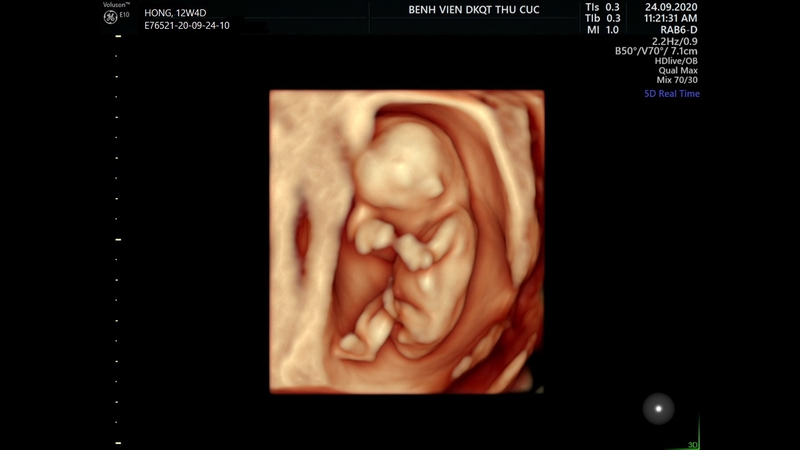

Khi xảy ra các thay đổi trong nhiễm sắc thể, nồng độ hCG và PAPP-A có thể tăng hoặc giảm so với mức bình thường. Khi phát hiện bất thường, bác sĩ sẽ tiếp tục thực hiện các biện pháp khác như siêu âm đo mờ da gáy và đo chiều dài mông đầu của thai nhi để đưa ra đánh giá chính xác hơn về tình trạng sức khỏe của thai nhi.

Xét nghiệm Double Test được coi là một trong những biện pháp sàng lọc thai kỳ, thường được thực hiện ngay trong tam cá nguyệt đầu tiên. Nó kết hợp với siêu âm đo độ mờ da gáy, tuổi mẹ và các yếu tố khác để đánh giá nguy cơ mắc Hội chứng Down, Edward, Patau và các dị tật khác. Phương pháp này không xâm lấn và đảm bảo an toàn cho mẹ và bé, đồng thời vẫn đánh giá được nguy cơ dị tật mà thai nhi có thể mắc phải.

Xét nghiệm Double Test từ tuần bao nhiêu? Việc thực hiện xét nghiệm Double Test nên diễn ra trong khoảng thời gian thai nhi 11 - 13 tuần, tức là vào tuần thứ 12 của thai kỳ, trong quý I của thai kỳ.